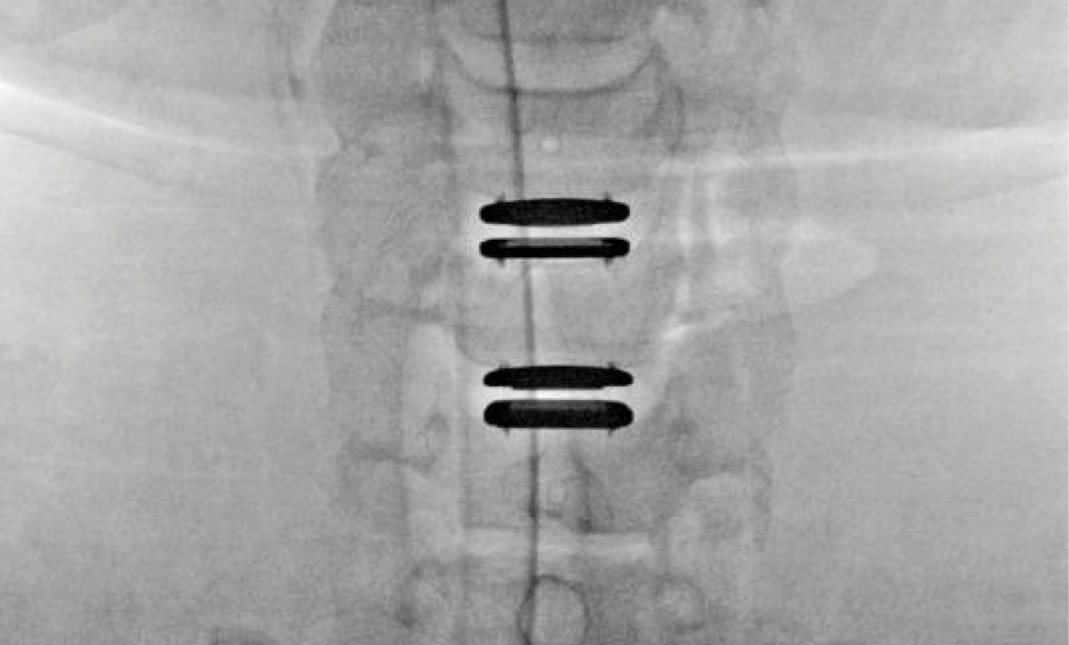

Upon examination, the patient had good motion on flexion-extension, so fusion was not considered at all. My operative plan was to use prodisc cervical devices and replace both discs at C4-5 and C5-6, giving me the flexibility to use either a domed or flat implant.

During the procedure, prodisc C Vivo fit well within the C4-5 concave endplate. I expected to use a flat endplate prodisc C SK at C5-6, however I trialed the domed prodisc C Vivo and it actually looked good, so I unexpectedly used matching implants.

It was very helpful to have the flexibility to use either a flat or a domed implant at either level. Having the different size options available to truly match patient anatomy that the Match-the-Disc™ System provides enabled me to avoid having to alter the patient’s anatomy to fit the device.